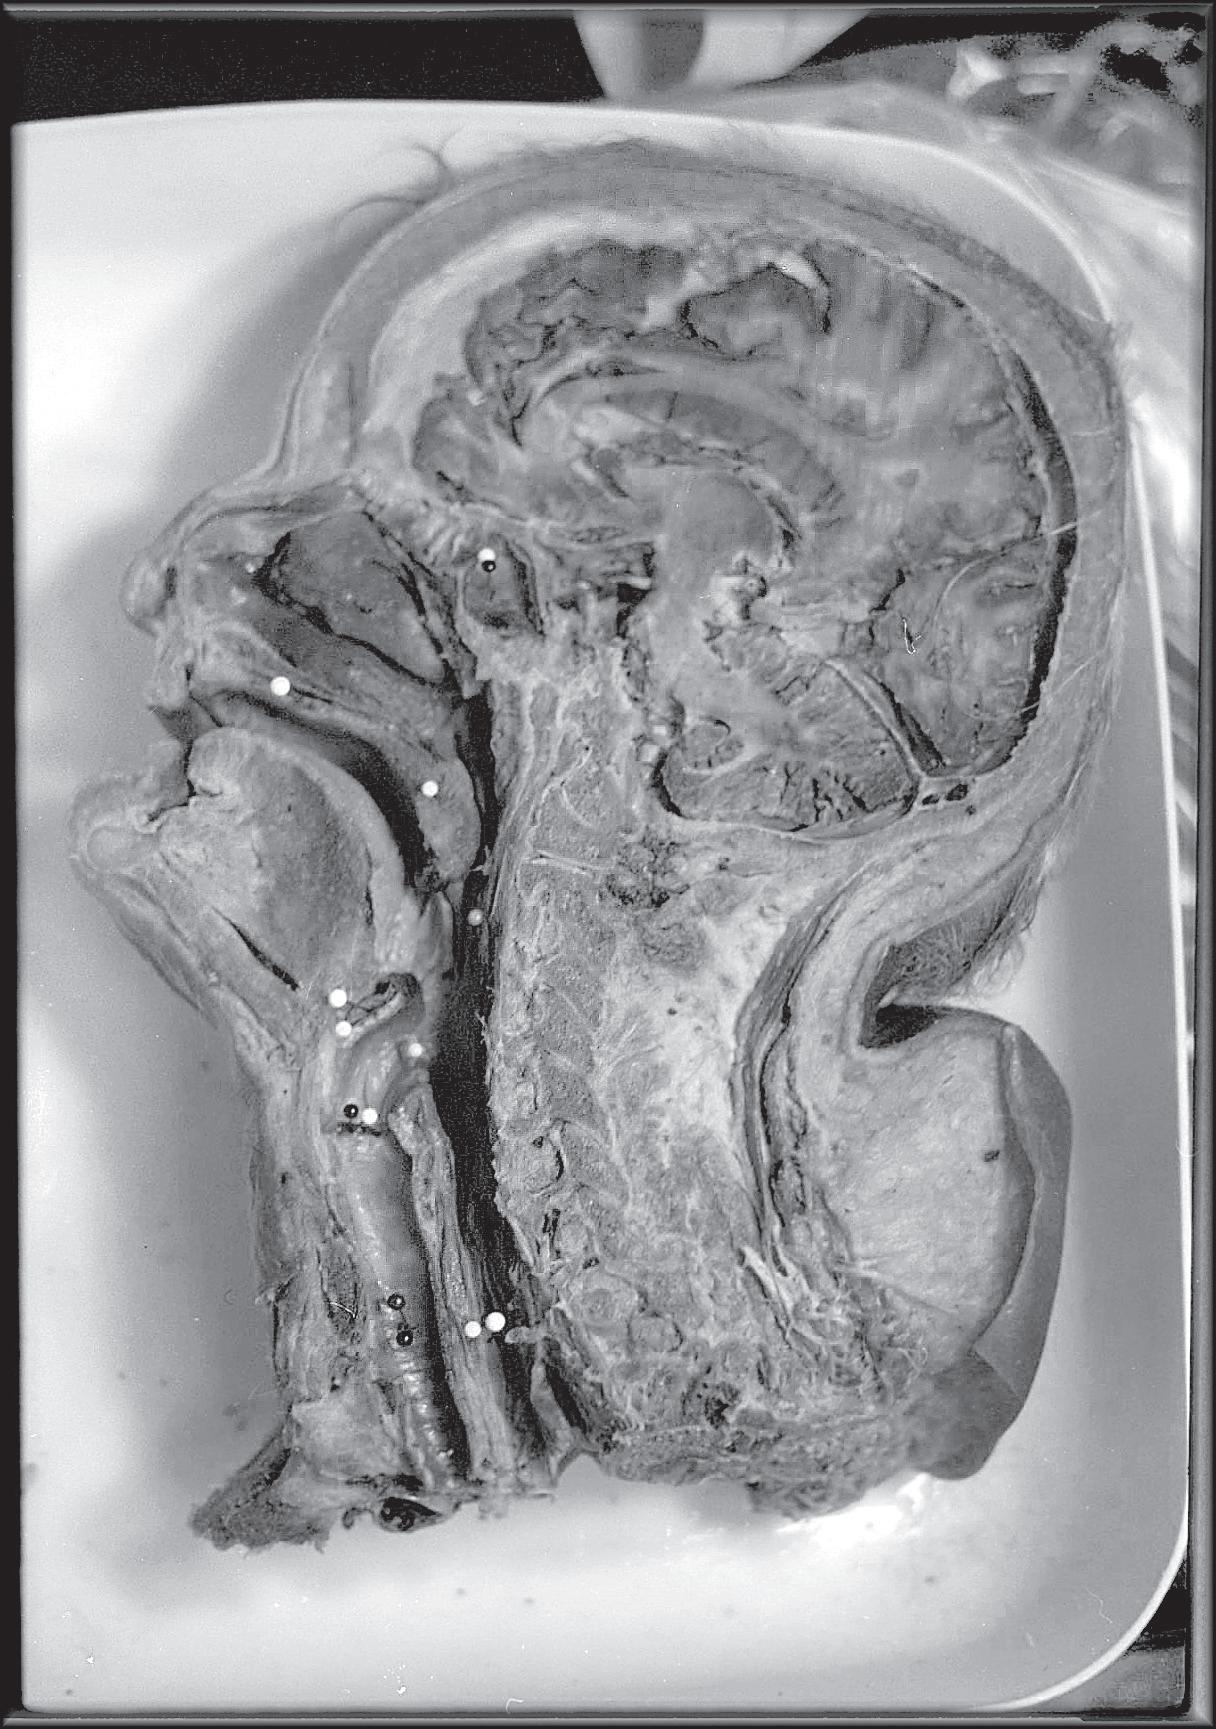

UVM faces a decline in body donations to science BY KEN PICARD

The University of Vermont wants you — or, more accurately, your remains once you’ve shuffled off this mortal coil.

It’s not the kind of information medical schools typically advertise in a local newspaper. Then again, this isn’t a typical year. For the first time in anyone’s memory, UVM has a critical shortage of cadavers. And if the number of donations doesn’t pick up by January, the university will have to start hunting around for dead bodies.

Rod Parsons chairs UVM’s anatomy and neurobiology department. Appropriately enough, he’s also director of the university’s Anatomical Gift Program — a position he’s held for 30 years. Parsons notes that donations are down this year by about half: from an average of 35 to 45 bodies annually to 20. That could create a problem for students in the spring semester.

Compounding the situation is the fact that demand for cadavers has actually grown as UVM has expanded its medical training and research programs. The College of Medicine has 114 students, up from 75 when Parsons became chair in 1979. That number doesn’t include the students who are working toward graduate degrees in neuroscience, those training to become physical therapists, the residents who need corpses on which to

practice new surgical procedures, or other medical researchers working at the Burlington campus.

Moreover, Parsons notes, most of UVM’s donated bodies come from within the state, and Vermont’s population growth hasn’t kept pace with the school’s burgeoning demand for corpses.

Then again, Parsons suggests a more plausible reason for Vermont’s declining number of donors: the cost associated with giving one’s body to medical science. Although UVM absorbs nearly all the expenses, including cremating and returning the remains to families, the cost of transporting the deceased to the medical school is still incurred by the next of kin. In tough economic times, that expense may be too much for some Vermonters to shoulder.

In fact, it can be considerable, depending on where the person dies and who handles the body. According to a 2007 price survey of local funeral homes conducted by the Vermont Funeral Consumers Alliance, the cost of body donations ranges from $525 to $1790, depending on the funeral home. And that figure doesn’t include other fees tacked on by the mortician, such as get-

THE COST OF TRANSPORTING THE DECEASED TO THE MEDICAL SCHOOL IS STILL INCURRED BY THE NEXT OF KIN. IN TOUGH ECONOMIC TIMES, THAT EXPENSE MAY BE TOO MUCH FOR SOME VERMONTERS

Parsons isn’t certain what explains the record-low body count, though he has a few theories. It may be due to an encouraging trend: Vermonters are healthier and living longer. Or it could be a matter of chance: The number of anatomical donations fluctuates from year to year, ranging from 32 to 50. This year may be a statistical aberration.

Another possible factor is that anatomical gift programs have gotten a bad rap in recent years owing to a few “bad apples.” Although UVM’s program has a spotless ethical record, the same can’t be said for all medical schools. For example, in 2007, the director of UCLA’s Willed Body Program was arrested for profiteering from the sale and transportation of bodies and parts. Such revelations, though rare, do little to instill public trust in an industry that is largely unregulated.

ting copies of the death certificate or storing the body overnight.